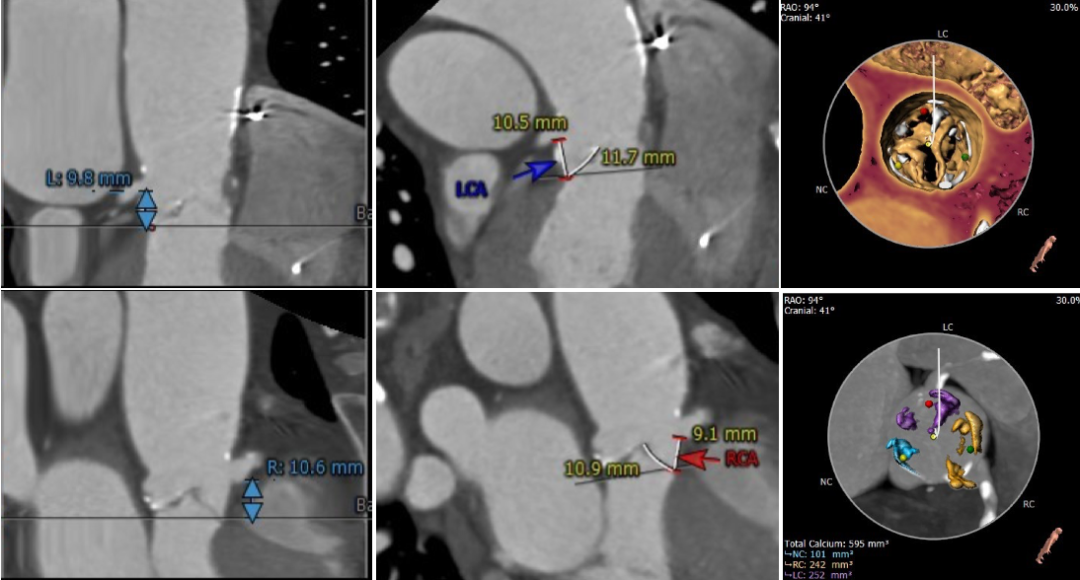

术前CT显示为三叶式主动脉瓣,瓣膜钙化、瓣叶增厚,伴左-右及左-无瓣叶融合,左右冠脉开口较低,瓣叶冗长,冠脉闭塞风险高,同时合并冠状动脉及主动脉的严重钙化。

瓣环水平夹角为52°,降主动脉全程满布钙化斑块,双侧股动脉散在钙化斑块,血管入路直径偏小,最细处仅为5.5mm。

主动脉根部测量

冠脉高度、瓣叶长度及钙化测量

瓣环上多平面测量

外周血管及主动脉弓解剖

南京市第一医院张俊杰教授团队在手术前对患者进行整体评估讨论,本例手术最大的难点在于冠脉阻挡风险高和外周血管直径偏细。根据冠脉高度、瓣叶长度、瓦氏窦宽度、钙化分布综合分析,为预防左右冠阻挡,术前预埋Guidezilla保护。